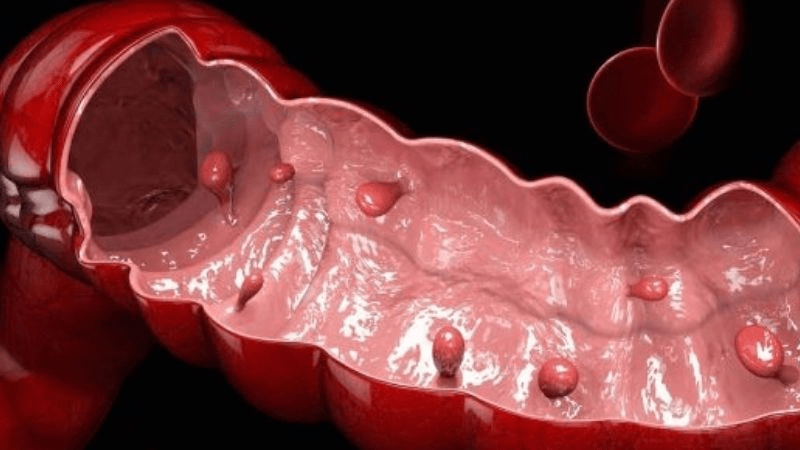

What Exactly Is a Colon Polyp—and Why Should You Care?

A polyp is an abnormal growth of tissue in the colon. Some are pedunculated—meaning they grow on a little stalk or stem, like a tiny mushroom protruding from the colon wall. Others are sessile, sitting flat like a dome. While most start harmless, certain types carry a higher risk of developing into colon cancer over time. Only about 5-10% of polyps eventually turn cancerous, but with colorectal cancer still ranking as the third most common cancer in the US, prevention matters.

Turning 45 or older often means facing unexpected hurdles in gut health. Surveys show many adults discover polyps during screening, and the emotional weight hits hard when you realize these growths signal long-term inflammation or dietary patterns that need attention. It’s frustrating when you eat “healthy” yet still worry about hidden risks—sound familiar? But it’s not just about polyps themselves; unchecked inflammation can stimulate further growth, and poor gut barrier function may allow toxins to linger.